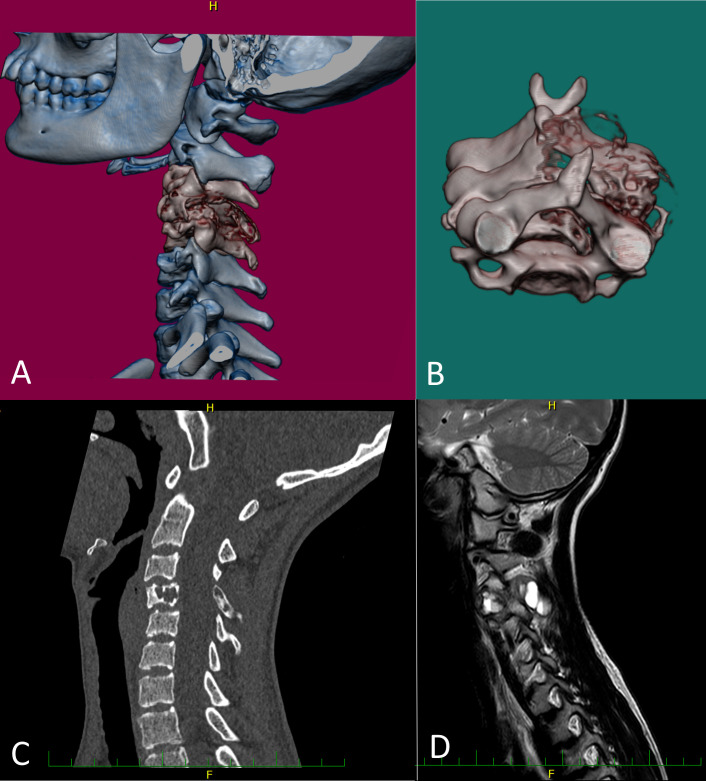

Aims: The purpose of this study is to report novel and unusual USP6 fusion partners in aneurysmal bone cysts (ABCs). These findings may be useful in routine diagnostics as well as in studying the biology of USP6-related disorders.

Methods: A cohort of seven patients diagnosed with ABC examined between 2014 and 2023 at Motol University Hospital in Prague was included into this retrospective non-randomised study. All cases were analysed using histopathological evaluation, immunohistochemistry and Anchored multiplex RNA methods. Demographic characteristics and clinical data were also analysed.

Results: We identified two novel (ZFX and IP6K2), three unusual (MEF2A, EIF1 and COL1A2) and two common (CDH11) fusion partners with USP6 gene among all seven cases of ABC.

Conclusions: Cases in our study were diagnosed as ABCs due to characteristic clinical and morphological presentation. However, not all cases are as self-evident, and molecular testing is necessary. The identification of these gene alterations can be useful in distinction between true ABC and ABC-like changes among many benign and malignant bone tumours.